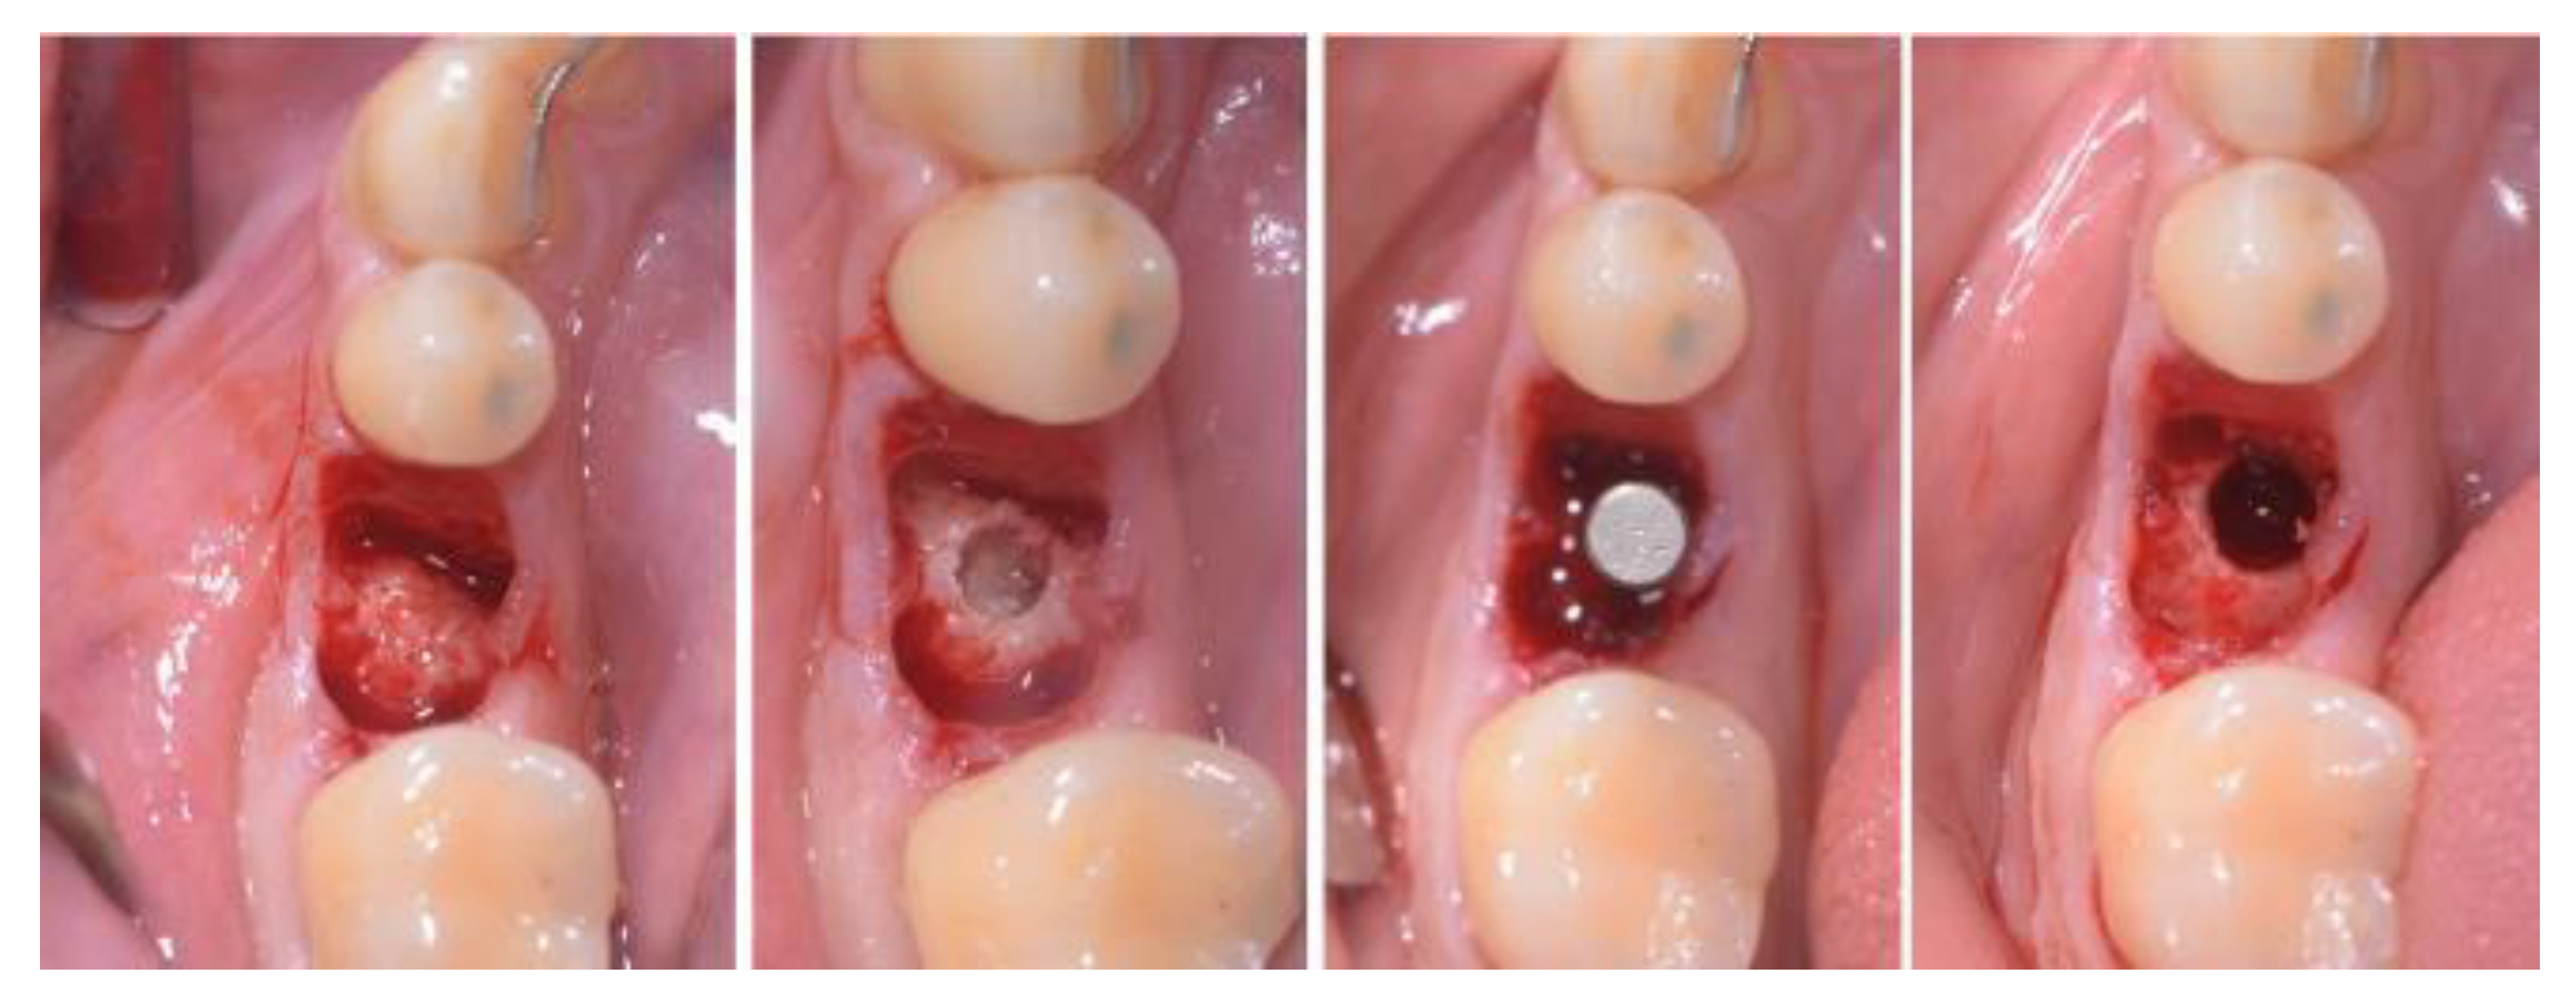

2.3. Treatment Procedure

- Case 2: